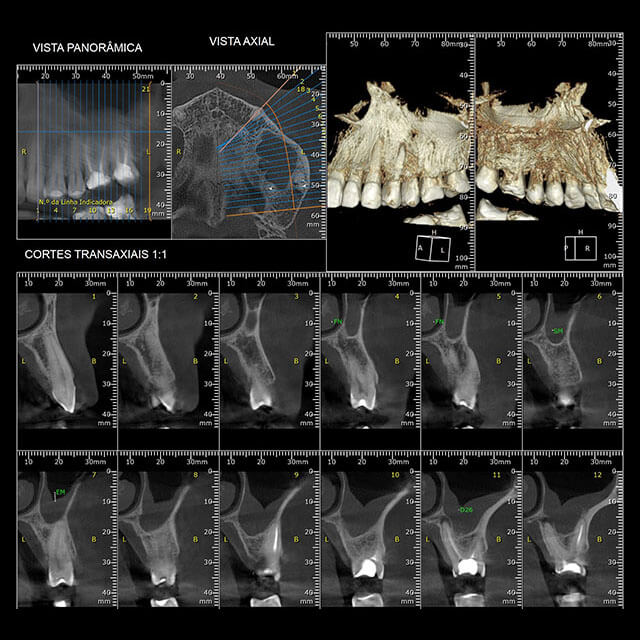

Também chamada de tomografia computadorizada de feixe cônico ou volumétrica, a tomografia Cone Beam é um método de captura radiográfica de imagem em três dimensões (3D).

Para conseguir as imagens, o aparelho conta com um feixe cônico de radiação e um receptor, que giram em 360° um única vez na região de interesse.

A documentação ortodôntica é um conjunto de exames composto por radiografias, fotografias intra e extra-bucais, modelos em gesso das arcadas dentárias, análises cefalométricas e de modelos computadorizados que o dentista solicita para ter uma visão abrangente e detalhada do caso de seu paciente.